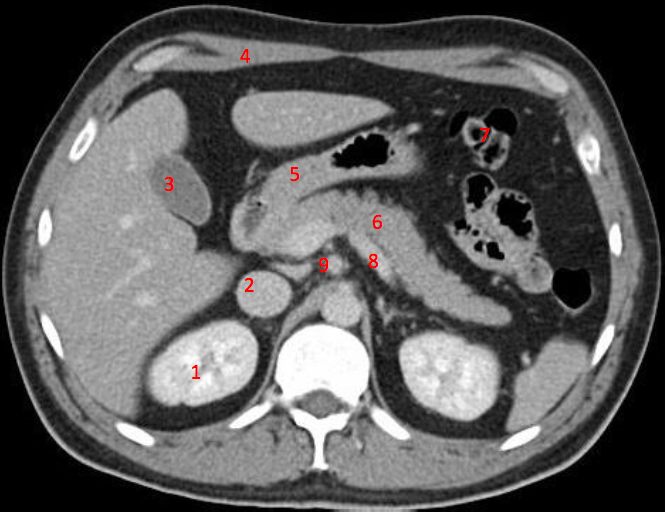

3

Number 1?

R kidney

13

Number 4?

Head of pancreas

14

Rt diaghragmatic crus

16

Number 2?

IVC

22

Number 6?

Descending colon

24

Number 8?

25

Number 7?

Abdominal aorta

26

Rt erector spinae muscle

29

Lt common iliac artery

30

Body of pancreas

40

Lt iliac blade/ilium

44

Rt rectus abdonimalis muscle

45

Rt psoas muscle

47

Number 10?

Rt kidney

48

Number 5?

Duodendum

49

Aorta

50

Ascending colon

51

Rt gluteus muscle

54

55

Caecum